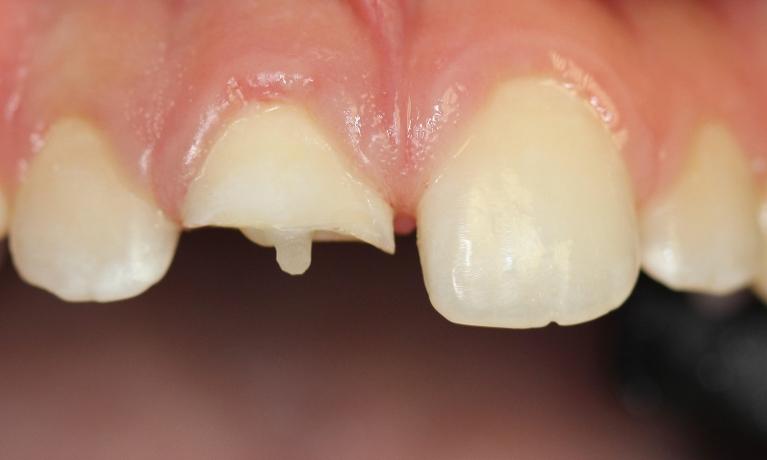

After this tooth was chipped, we placed composite bonding with the aid of our Solea Laser! This procedure used no shots or drills and there was no removal of tooth structure!